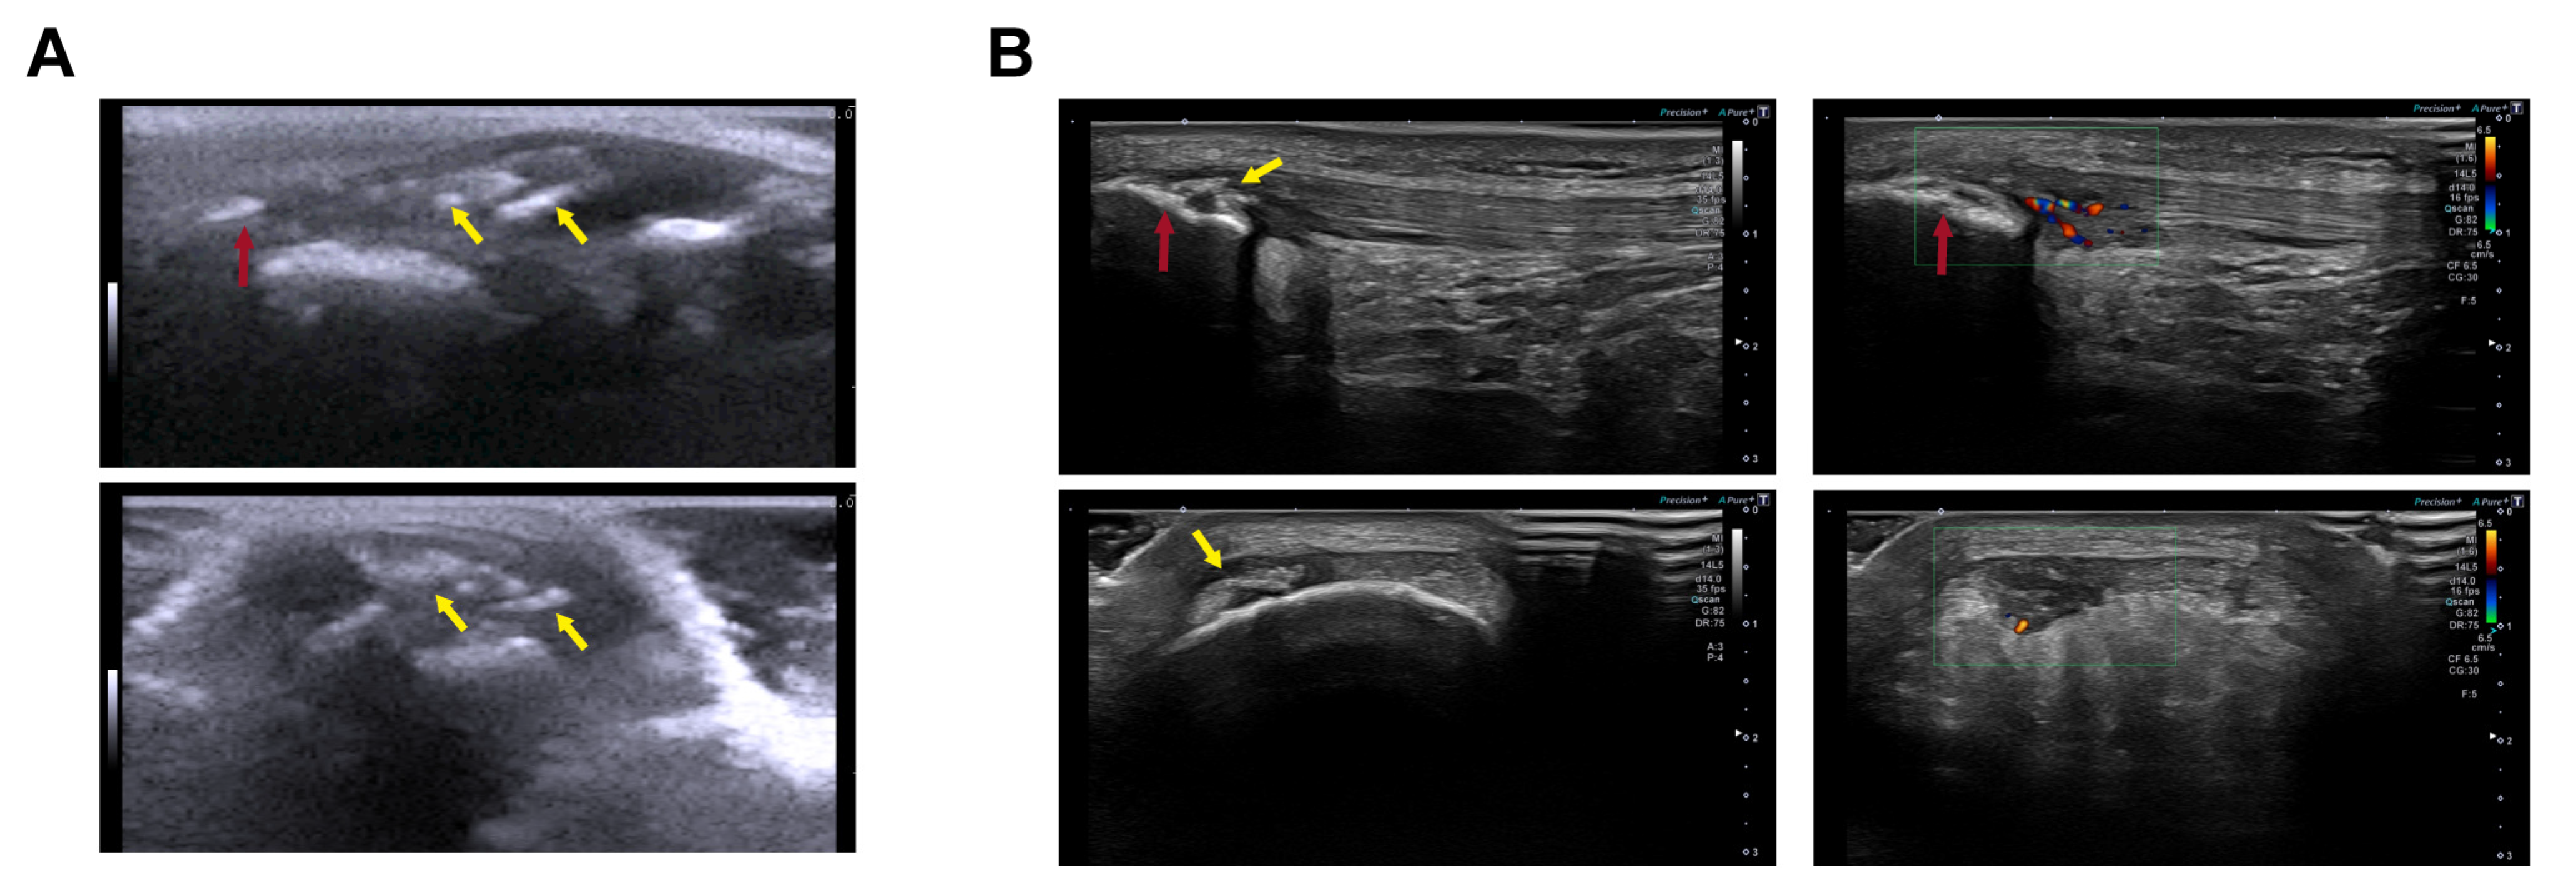

Additionally, we evaluated similarities between our rat model of patellar tendinopathy induced via the injection of the collagenase–Pluronic mixture and observations in human athletes. The evaluation was performed by comparing US images obtained from the rat model with those acquired from professional basketball players. As shown in Figure 6, we demonstrated that our patellar tendinopathy model in rats faithfully reproduces the characteristics observed in athletes during the US evaluation. In our rat model, we observed the presence of inflammation, along with a significant increase in the size of the tendon and the development of intra-tendinous calcifications 2 months after injury (Figure 6A). The echogenic signs detected in these rats closely resembled those observed in the patellar tendons of professional basketball players. These signs included an increase in tendon size, neovascularization with blood vessel infiltration, and calcifications in the proximal insertional region or within the patellar tendon itself (Figure 6B).

Figure 6.

US in vivo imaging of tendon intra-tendinous calcifications for comparison between the collagenase–Pluronic treated rat patellar tendinopathy model and the images from human professional athletes. The red arrows indicate the patella, and the yellow arrows indicate intra-tendinous calcifications. The green rectangle indicates the area where Doppler US was analyzed. Longitudinal views (upper panels) and transversal views (lower panels) of the patellar tendons are shown. (A) Representative US images of the rat tendinopathy model at 60 days after injury, when intra-tendinous calcifications and substantial tendon swelling can be observed. (B) Representative US images of human patellar tendinopathy (images from a 23-year-old male professional basketball player), showing the presence of calcifications in the proximal region of the patellar tendon ((B), left panels), and Doppler US imaging indicating neovascularization with infiltrating blood vessels ((B), right panels).